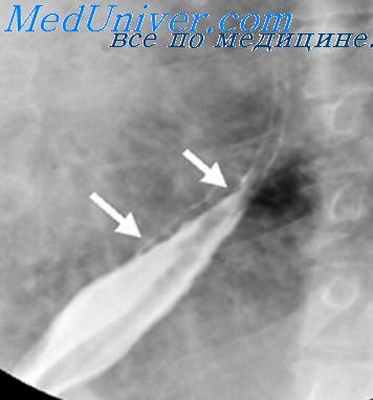

Опухоли пищевода. Рентгенологическая картина при опухолях пищевода зависит от характера процесса (доброкачественный или злокачественный), особенностей роста (экзофитный, эндофитный, смешанный), стадии развития (с изъязвлением или без него), локализации, а также нарушений функции, вызванных опухолью. Сама опухоль отображается на рентгенограмме в виде дефекта наполнения или сужения просвета пищевода, а вызываемые ее ростом изменения сказываются на картине рельефа слизистой оболочки (отклонение или разрушение складок), эластичности стенки и ее сократительной способности. При доброкачественных опухолях дефект наполнения имеет правильную форму (округлую, овальную или полуовальную) и в зависимости от проекции исследования может быть центральным, краевым и значительно реже — циркулярным. Контуры его, как правило, четкие, не всегда ровные. Во время акта глотания такой дефект легко смещается кверху вместе со стенкой пищевода. При преимущественно экзоэзофагеальном росте и значительных размерах опухоли на уровне дефекта наполнения на фоне заднего средостения может определяться дополнительная тень.

Именно отсутствием разрушения отклоненных или сглаженных складок слизистой оболочки в зоне расположения опухоли доброкачественные опухоли отличаются от полипоподобного рака. При доброкачественных опухолях практически почти полностью сохраняются эластичность стенки на уровне поражения и ее сократительная способность, а супрастенотическое расширение просвета над опухолью отсутствует. В связи с этим значительной задержки бариевой взвеси здесь не наблюдается и стенки пищевода растягиваются бариевым комком симметрично, а пораженный участок переходит в нормальную зону постепенно, без резких границ. Состояние эластичности стенок при доброкачественных опухолях пищевода особенно отчетливо определяется при рентгенокиносъемке [Кевеш Л. Е., 1965; Рабкин И. X. и др., 1969], а также при использовании видеомагнитной записи получаемого изображения.

Если во время исследования пищевода дефект наполнения не занимает краеобразующего положения, то на уровне крупной доброкачественной опухоли может определяться веретенообразное расширение тени пищевода, обусловленное растяжением непораженных его стенок массой опухоли. При этом истинного увеличения просвета пищевода нет. Более того, он явно сужен опухолью, что отчетливо видно во время прохождения бариевой взвеси. Достаточно в процессе исследования изменить проекцию, чтобы избежать ошибочного истолкования данной скиалогической картины.

Иногда доброкачественная опухоль изъязвляется. В таких случаях обычно в центре дефекта наполнения выявляется стойкое депо бария (ниша) неправильной формы. Истинное изъязвление доброкачественной опухоли дифференцируют от скоплений (депо) бариевой взвеси между отдельными возвышениями на неровной поверхности опухоли или между вдающимися в просвет пищевода узлами и его нормальной стенкой. В отличие от изъязвляющейся опухоли указанные выше депо бария непостоянны: в процессе исследования форма ч величина меняются. Доброкачественные опухоли пищевода необходимо дифференцировать от варикозно расширенных вен, инородных тел, пузырьков воздуха, окруженных барием, и злокачественных опухолей.